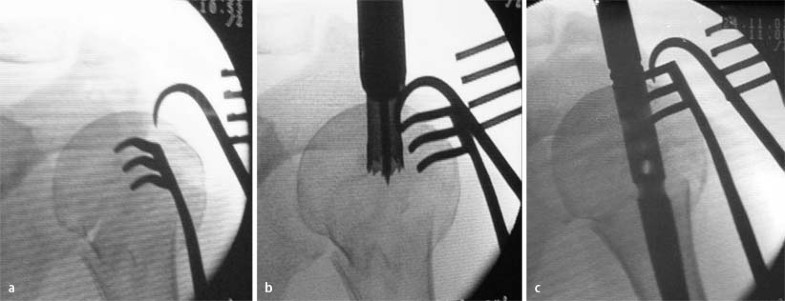

Verriegelung des T2-PHN über Zielbügel, a Schema, b anatomische Schraubenposition, c in situ

a Reposition mit dem Einzinker, b Eröffnen des Nageleintrittspunkts mit der Hohlfräse, c Einführen des Nagels